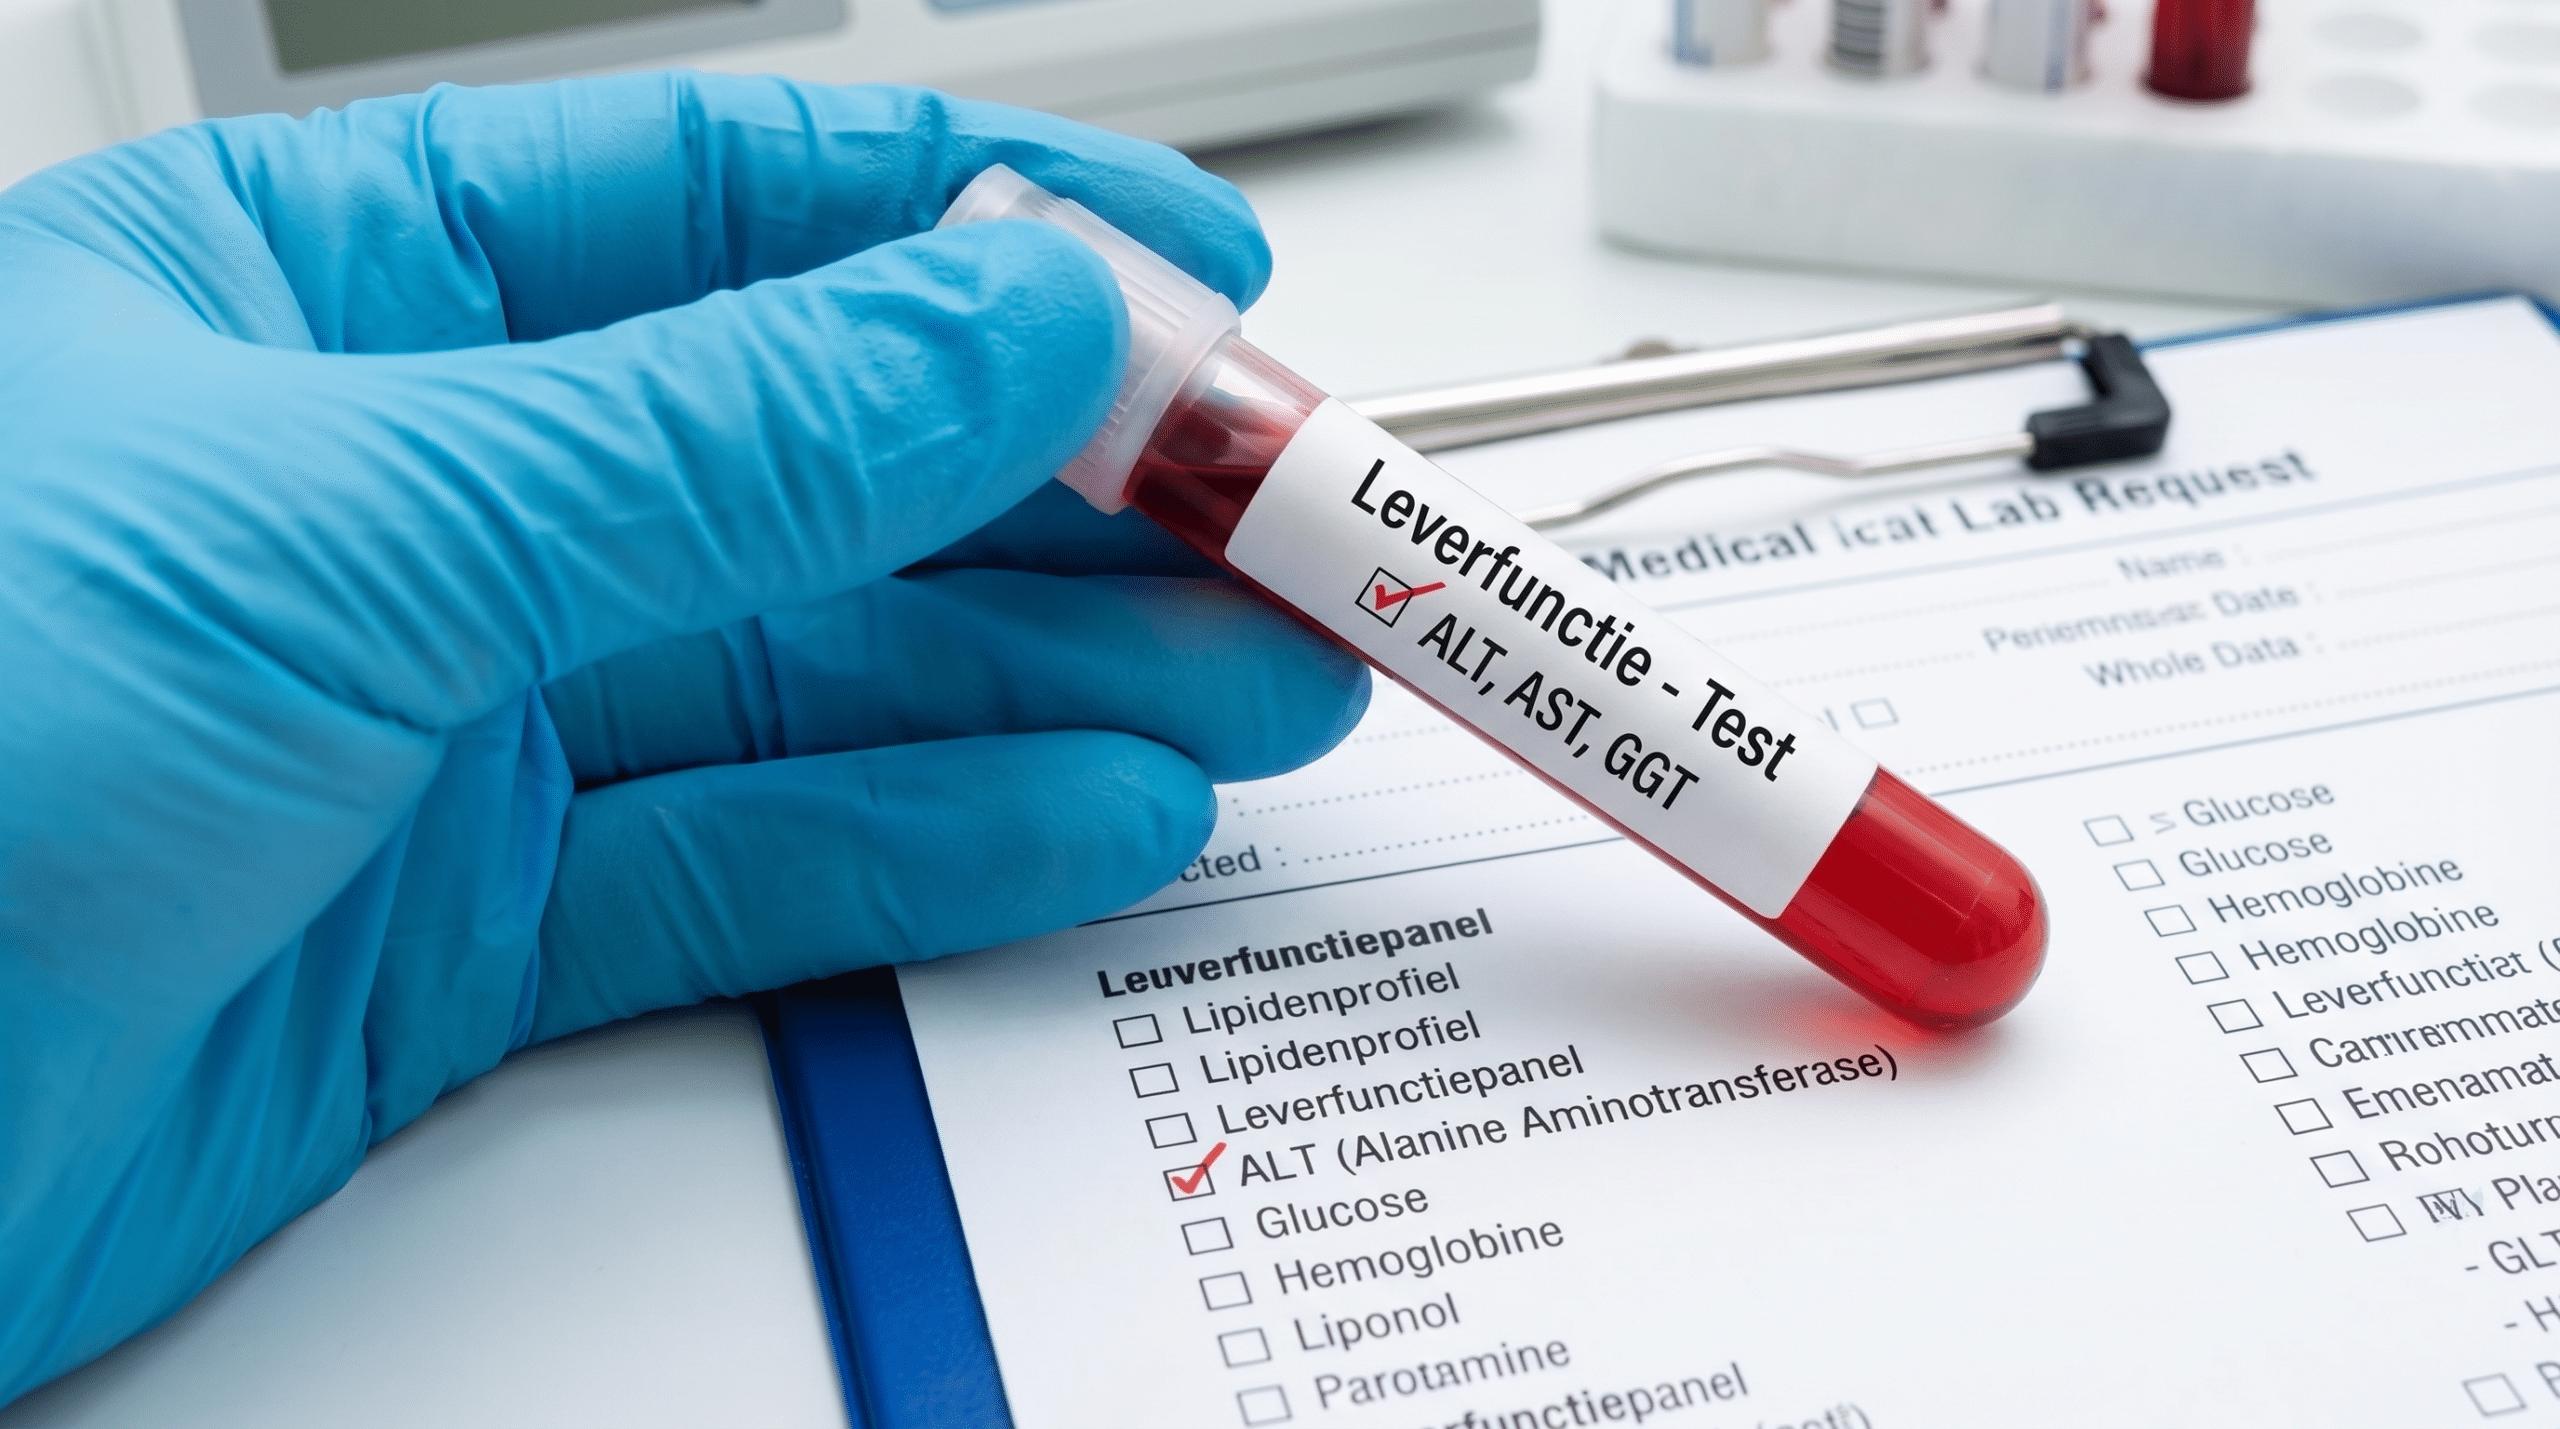

Een systematische review en meta-analyse gepubliceerd in PubMed (2024), waarbij 26 gerandomiseerde gecontroleerde studies met in totaal 2.375 NAFLD-patiënten werden geanalyseerd, toonde aan dat silymarine de leverenzymen ALT en AST significant kan verlagen en de histologische leverbevindingen kan verbeteren bij mensen met leververvetting.